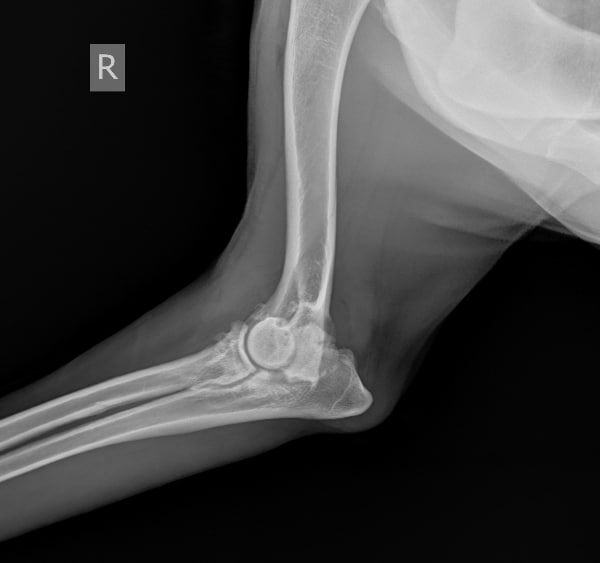

Вот так выглядит артроз локтевого сустава - правый сустав, левый сустав в порядке

Вот так выглядит артроз локтевого сустава - правый сустав, левый сустав в порядке.